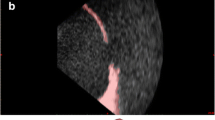

Creation of a cardiac model. CMR images were obtained from an adult patient with transposition of great arteries status post Mustard atrial switch procedure, followed by image segmentation, creation of a digital model and, finally, a printed model. a Three orthogonal views (axial, sagittal, and coronal) of the 3D dataset with segmentation masks overlaid in color. Noted are the systemic venous baffle (blue mask), left ventricle (orange mask), pulmonary arteries (purple mask), pulmonary venous baffle (red mask), right ventricle (yellow mask), and aorta (green mask). b The segmentation software reconstructs a 3D digital object from each respective segmentation mask. c A combination of Boolean functions, smoothing, and wrapping functions are used to finalize the 3D digital model. Cuts are made onto the model to display internal anatomy. d The 3D digital models are transferred to a 3D printer and physical components are printed as shown. Each piece is held together by magnets. The internal chambers are also painted with color to represent the flow of saturated and desaturated blood (Color figure online)